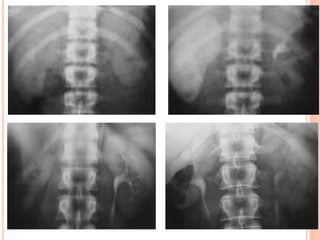

URETERS

- peristalsis.

- Stasis of contrast.

- Medial deviation.

- Lateral deviation.

- Anatomic narrowing.

- Ureter diameter (8mm).

- Filling defect.

 Medial deviation of the ureter should be considered

when the ureter overlies the ipsilateral lumbar

pedicle.

 lateral deviation should be considered when the

ureter lies more than 1.5 cm beyond the tip of the

transverse process.